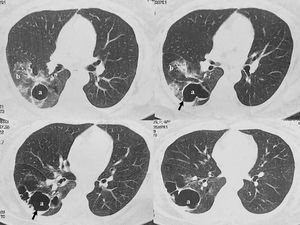

Case reportA 49-year-old female with bronchiectasis and a cavity secondary to tuberculosis suffered from multiple episodes (total of six) of pneumonia and hemoptysis between 2020 and 2022, which had not a clear diagnosis before her admission to the Hospital Naval Dr. Pedro Mallo. Mycobacterium tuberculosis disease occurred when she was 5 years old. Diagnostic tests for hepatitis B and C were negative. Likewise, human immunodeficiency virus test was non-reactive. In January 2023, a CT scan of the thorax revealed, as a sequela, the presence of a 40×71mm cavity in the lower lobe of the right lung that contained a small volume of fluid associated with bronchiectasis (Fig. 1). As the spirometry result was within normal parameters, a pulmonary lobectomy was performed. The tissue removed was sent for histopathological study and microbiological culture. Once the microorganism was properly identified, the patient was treated with voriconazole, with a loading dose of 800mg twice a day the first day and, subsequently, 200mg every 12h for 6 months. The patient responded well to therapy and remained asymptomatic. Control CT scans were done and, as expected, post-surgical changes with minimum fluid in the fissure adjacent to the surgical line were observed.

Scedosporium is widely distributed in environmental sources.16 In the present report, the fungal infection was localized in the lung.17 This single finding was in line with the results obtained by CT scans of the thorax. In pulmonary colonization, the predisposing condition is usually the existence of a preformed bronchiectasis, cavity or cyst, most of which are caused by species of the genus Aspergillus, especially Aspergillus fumigatus. However, other genera such as Fusarium, Acremonium or Scedosporium are frequently isolated.5,9,15,16,20 Kantarcioglu et al. highlight the existence of post-tuberculosis cavitation as a major risk factor for acquiring pulmonary infections by the S. apiospermum complex.9 In histopathological observations of pulmonary colonization, Aspergillus species display a regular, dichotomous branching pattern, while Scedosporium strains exhibit a more irregular branching pattern (Fig. 2).10 However, different authors argue that S. apiospermum and Aspergillus look the same in histopathological analyses.7–9 Overall, it is always difficult to distinguish between them when examining the tissues.6